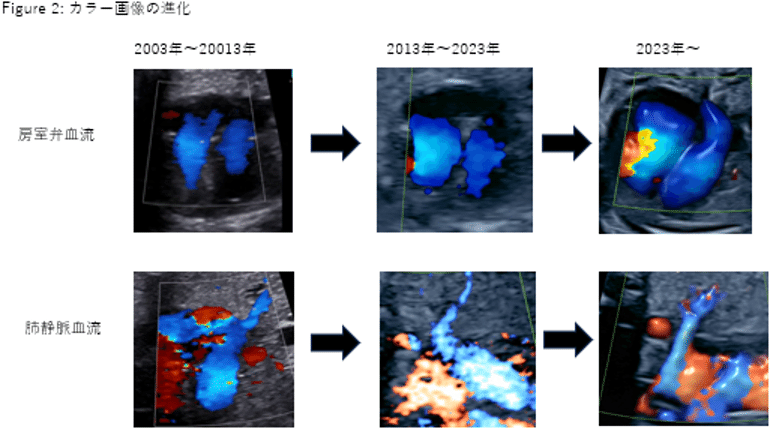

HOT ! 動画で見る・胎児心エコー診断 Amazon.co.jp: 動画で見る・胎児心エコー診断 3−カラードプラー

動画で見る・胎児心エコー診断 Amazon.co.jp: 動画で見る・胎児心エコー診断 3−カラードプラーの詳細情報

Amazon.co.jp: 動画で見る・胎児心エコー診断 3−カラードプラー。1-動画で見る・胎児心エコー診断 1 (位置異常,心拡大,センター。ここまで見える胎児心エコー検査|☆近大小児科すくすくナビ。ここまで見える胎児心エコー検査|☆近大小児科すくすくナビ。動画で見る・胎児心エコー診断 1.2.3川滝 元良DVD付 ほぼ未使用 ネーム印あり#川滝元良 #川滝_元良 #本 #自然/医療・薬学・健康

• Amazon.co.jp: 動画で見る・胎児心エコー診断 3−カラードプラー